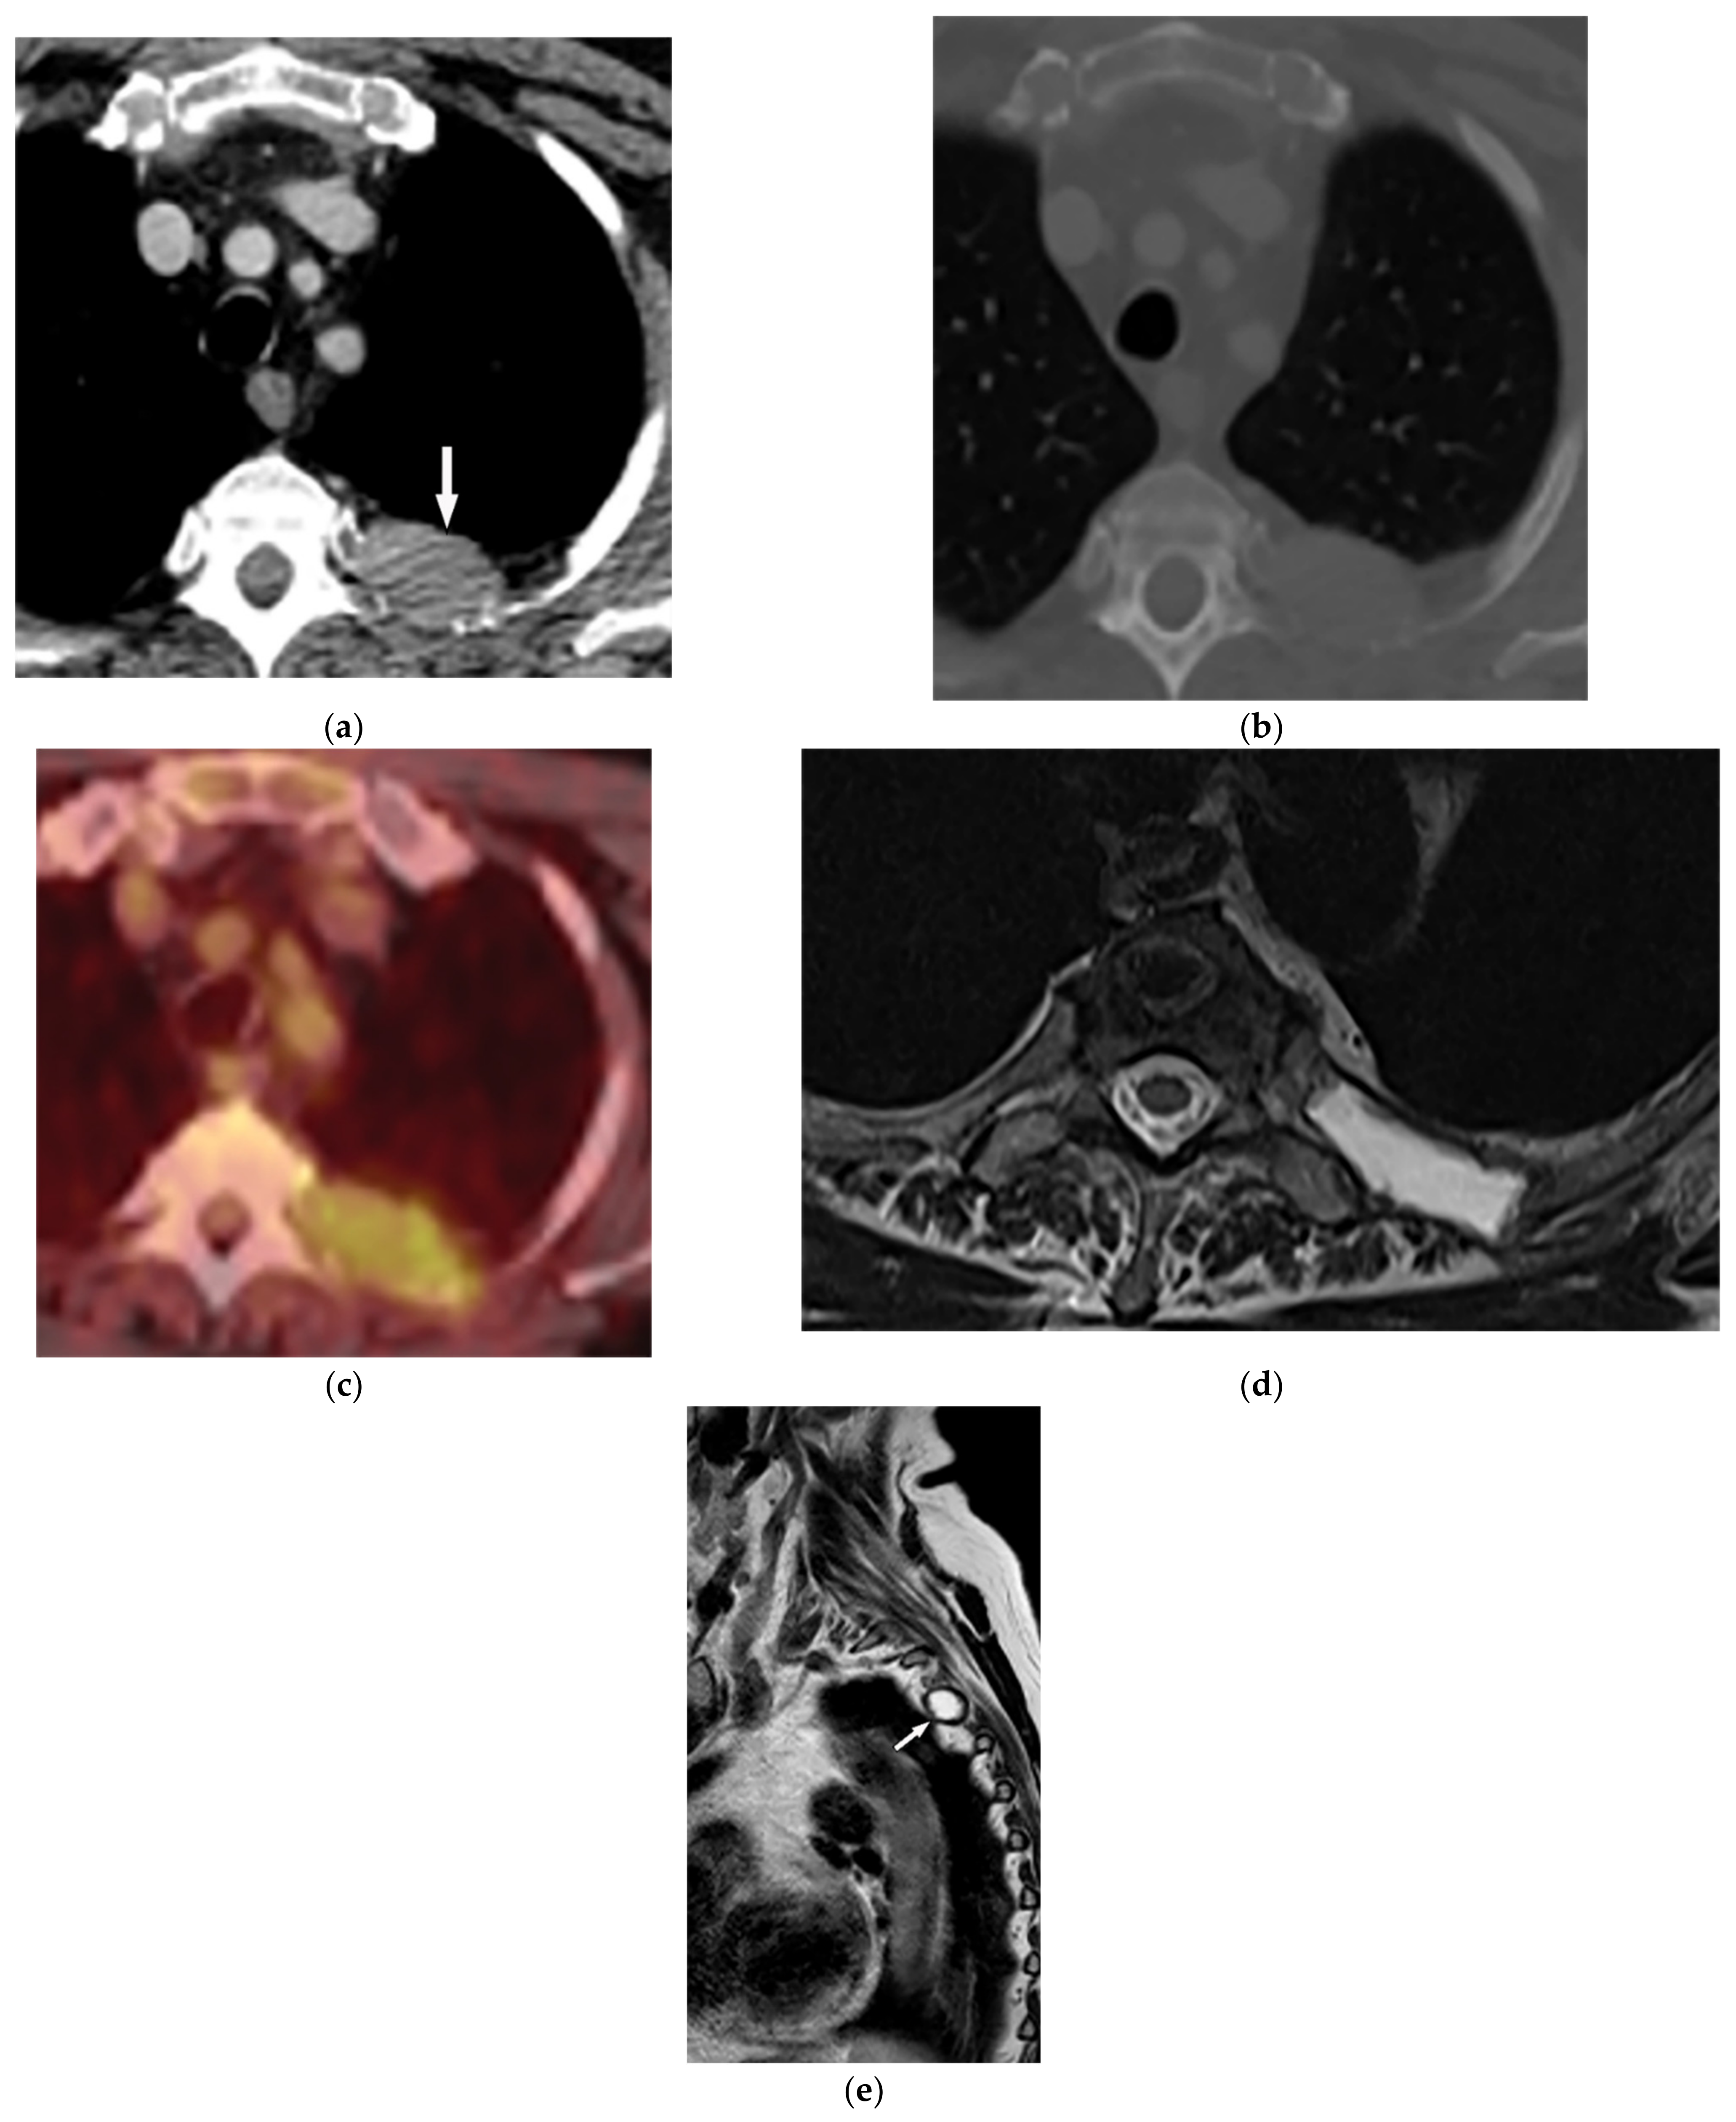

| Extramedullary hematopoiesis | Heterogeneous mass with internal foci of fat with lack of calcification. | T1W, T2W: heterogeneous with internal foci of hyperintensity in old lesions (representative of fat), the intermediate intensity with subtle or no enhancement in active lesions |